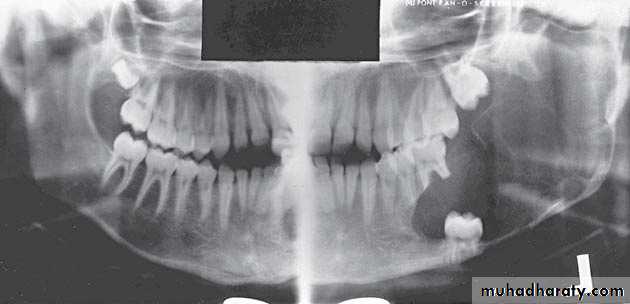

Large multilocular aneurysmal bone cyst

in the ramus with marked expansion andthe displacement of/8.

It is non-neoplastic ,exaggerated , localized, proliferative lesion of vascular tissue, containing giant cells.

It’s a variation of the central giant cell granuloma , can be diagnosed only by histological examination